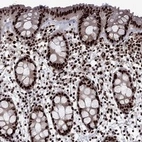

Immunohistochemical staining of human rectum shows strong nuclear positivity in glandular cells.